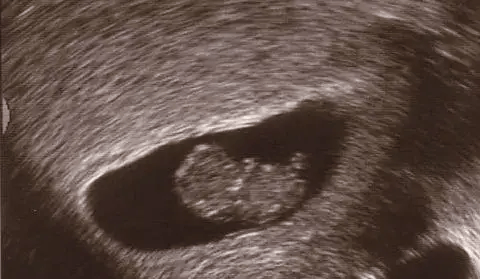

a baby human in the womb

"For you created my inmost being; you knit me together in my mother's womb."

Psalm 139:13

Week 7